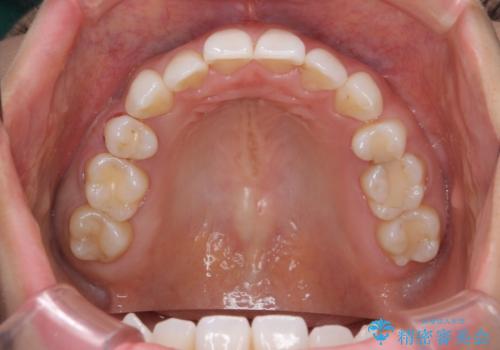

奥歯が欠けた セラミックインレーでの修復後、ナイトガード装着

- 右下の奥歯が欠けたとのことで来院されました。

欠けた部分にはセラミックインレーで修復処置を行い、今後の破折リスクを抑えるためにナイトガードを製作していきます。

- 右下7 セラミックインレー 77,000円/ナイトガード 33,000円費用は治療当時の料金となります